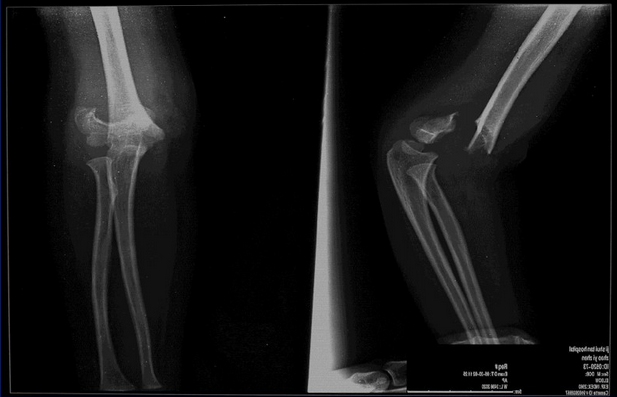

儿童肱骨髁上骨折位置

肱骨髁上骨折可分为伸直型、伸直尺偏型、伸直桡偏型和屈曲型。

1.伸直型

受伤时肘关节呈半屈位,手掌着地导致肱骨髁上部骨折,骨折的近侧端向前移位,远侧端向后移位。骨折线方向由后上向前下方斜形经过。移位严重者,骨折近侧端常损伤臂前方肌肉并对肱动脉造成损伤。

2.X线检查:可见骨折线。